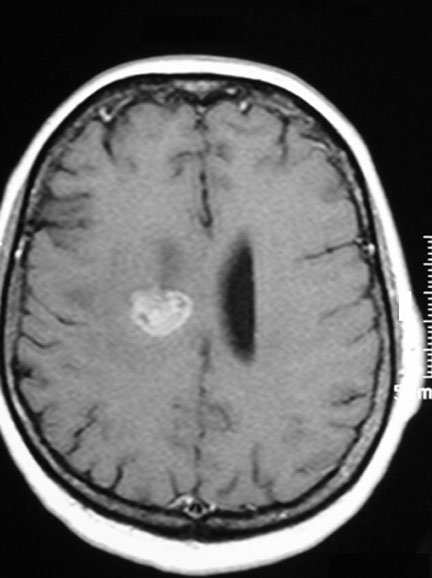

CASO 2 :Tratamiento de Metástasis de Cáncer de Pulmon con Radiocirugía Estereotáxica

Joven profesional con cáncer de pulmón y metástasis recurrente después de tratamiento en el extranjero. La resonancia magnética muestra al tumor rodeado de edema cerebral. El paciente presenta cefalea, convulsiones y trastornos del campo visual